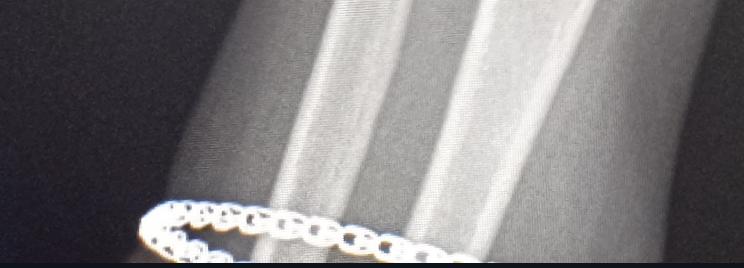

Здравствуй двачик, пишет вам простой рентгенолог из мухосранской поликлиники, сегодня я буду флексить зарплатой за ноябрь! Аж ПЯТЬДЕСЯТ ТРИ ТЫЩИ ПЕРЕВЕДУТ! С пруфом! А чего достигли вы? Ну и в доктора тож поиграем! Я буду вам картинки показывать, а вы пиздецомы находить! Найдите пиздецому на фтчк! Отчет еще по фог считать квартальный и годовой сегодня :-(